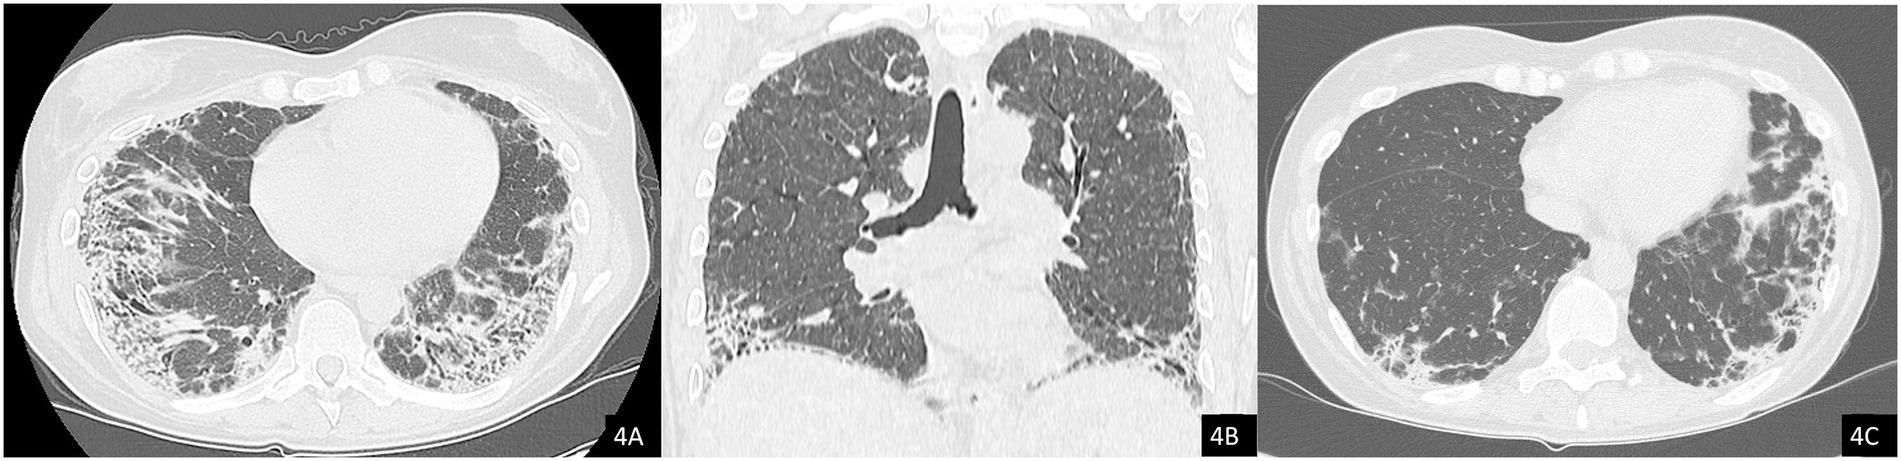

The chest HRCT performed at the end of April 2025 (Figure 4) demonstrated complete resolution of the previously observed pneumomediastinum. When compared with the August 2024 scan (Figure 4C), imaging revealed progression of fibrotic interstitial changes. Although comparison with interim scans was limited by the presence of pneumomediastinum, there were no current radiological signs of active inflammatory disease.

Figure 4. Axial (A) and coronal (B) chest CT images showing resolution of the pneumomediastinum and subcutaneous emphysema. Note the presence of interstitial lung disease (ILD) with a mixed NSIP/OP pattern and fibrosing features, including coarse reticulations, parenchymal distortion with traction bronchiectasis, and volume loss. (C) Comparison with a previous CT scan from 2024 demonstrates clear radiological progression of ILD.